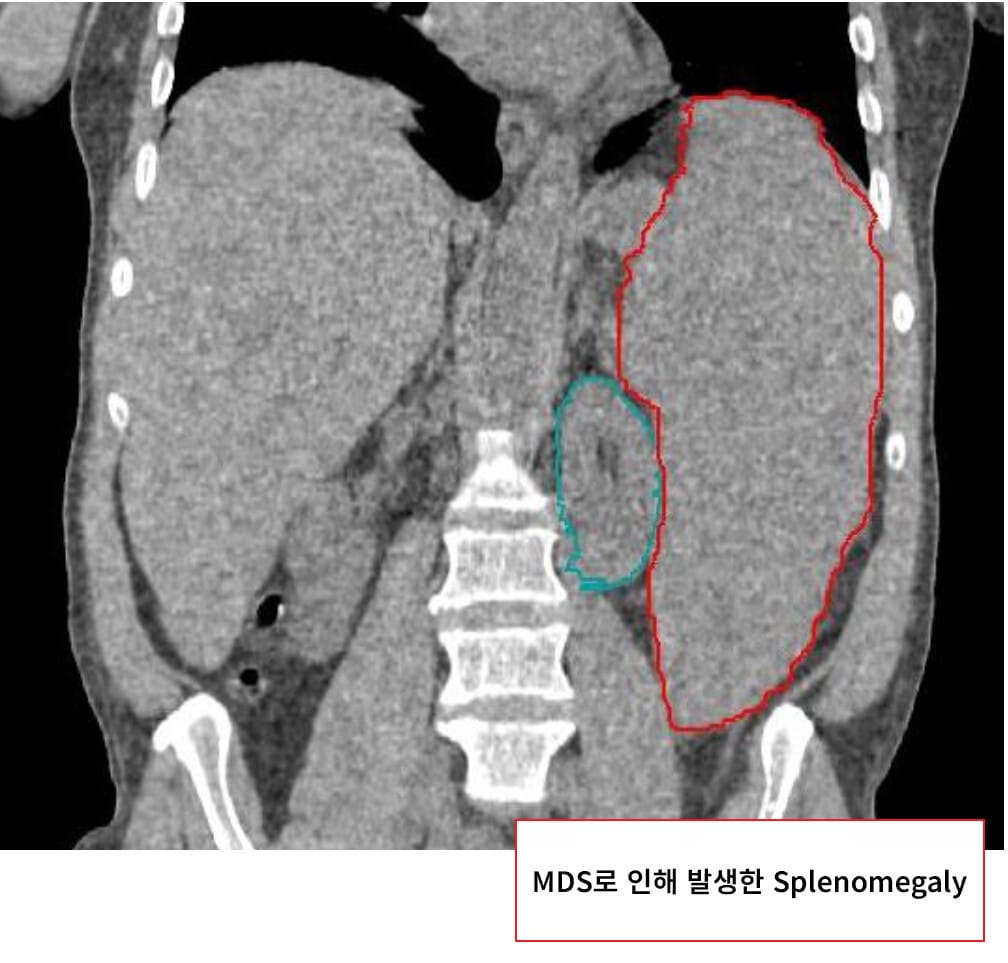

골수이형성증후군(Myelodysplastic Syndromes, MDS)는 조혈모세포의 분화 및 성숙 이상으로 인해 비정상적 혈구가 형성되고, 말초혈액에서 혈구 감소증(cytopenia)이 발생하는 클론성 조혈 질환입니다. 일부 환자는 급성골수성백혈병(AML)으로 진행할 수 있습니다.

혈구 감소증에 따른 증상이 주요하며, 초기에는 무증상일 수 있습니다.

| 피로, 창백, 호흡곤란 등 만성 빈혈의 증상이 흔하게 나타납니다. |